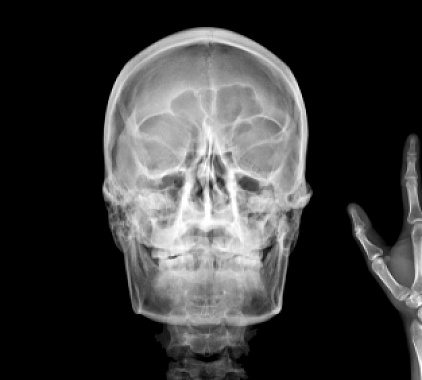

Как проходит исследование

Рентгенологическое исследование носоглотки совершенно безболезненно и не приводит к осложнениям. Время диагностики – не более 15 минут. Для того чтобы сделать снимок, нужно всего пару минут. По завершении процедуры больной может возвращаться к обычному укладу жизни.

Пациент ложится на кушетку на бок, голову плотно прижимает к кассете. Специалист проверяет правильность положения, оценивая два основных параметра: расположение условной линии между зрачками пациента по отношению к кассете под углом 90 градусов, расположение линии под глазами больного относительно кассеты под углом 90 градусов.

Далее врач уходит в смежное помещение. Получение снимков в ходе рентгена носоглотки осуществляется на вдохе, для этого пациент должен глубоко вдохнуть и не дышать на протяжении нескольких секунд. При необходимости дополнительно делают рентгеновский снимок в прямой проекции.

Фотогалерея

Рентген-аппарат